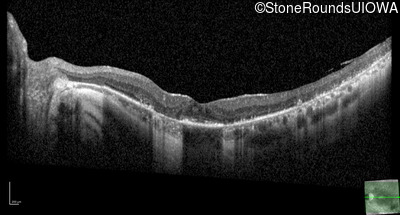

Optical Coherence Tomography - Right - 20/20

Exemplar / OCT Stack

OCT Stack